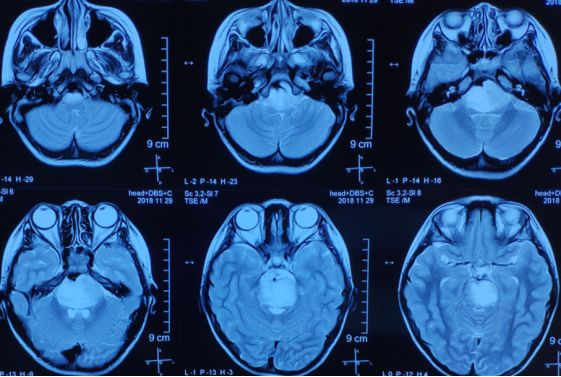

到院后,刘长青主任接诊,仔细询问了孩子的病史,并安排检查,根据检查结果:头颅CT提示脑干低密度占位。MRI提示脑干区占位,最大截面约4.4cm×3.1cm。诊断:脑干占位性病变,考虑胶质瘤可能。

手术前,需做头颅MRIT1、T2、增强T1的无间隔扫描,将数据融合后确定手术靶点。

手术当日,在全麻下为小蕊上头架,前往CT室,行头颅CT轴位的无间隔扫描,经测量、融合,确定坐标值及靶点。